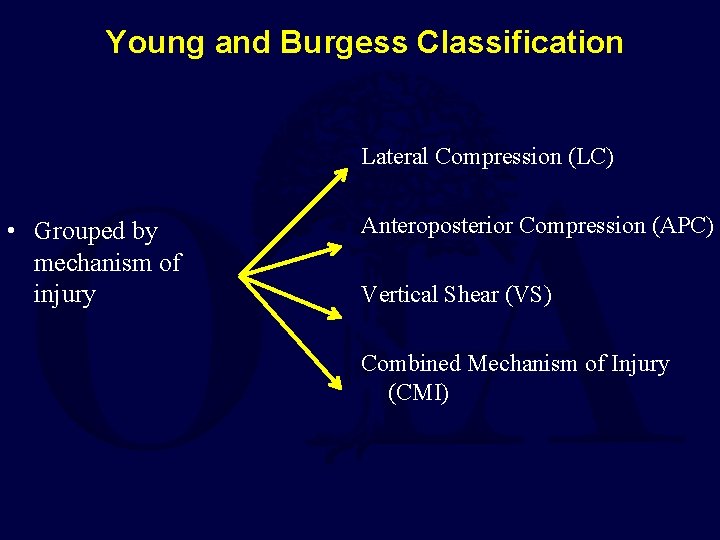

Young and Burgess Classification Lateral Compression (LC) • Grouped by mechanism of injury Anteroposterior Compression (APC) Vertical Shear (VS) Combined Mechanism of Injury (CMI)